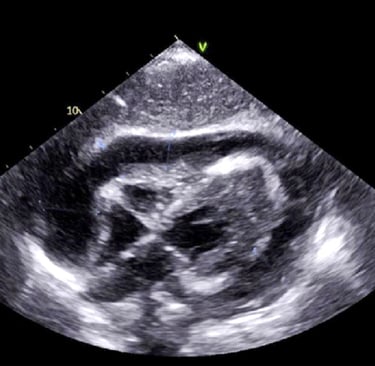

We start immediately at the bedside with probe in hand, introducing core FAST/RUSH protocols so you begin scanning on the very first minute of class. Hands-on practice is intense and structured: learners develop the hand-eye skills to acquire clear views quickly while faculty reinforce system controls, Doppler use, and targeted protocols that directly impact clinical decisions.

Scanning sessions are interwoven with short, high-yield discussions that tie anatomy and findings back to real patient scenarios. You repeatedly cycle through focused clinical targets — trauma windows, fluid detection, basic vascular access guidance — so that pattern recognition becomes automatic.

Hands-On POCUS- Point of Care Ultrasound